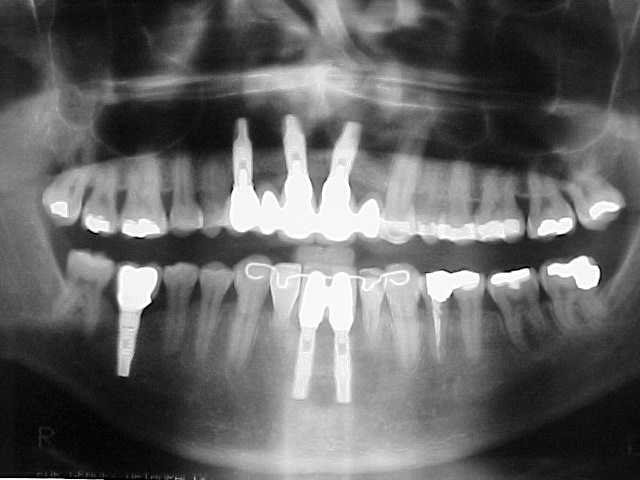

Preparação para instalação do "aparelho ortodôntico" (canino reconstruído em resina rápida autopolimerizável, retida por fio metálico sobre raiz residual)

Início do tratamento ortodôntico. Com a extrusão do canino estaremos induzindo ao nivelamento ósseo para a instalação de implante nesse local.

Munhões sobre réplicas dos implantes

Provisórios imediatos sobre implantes

Provisórios estéticos guia anatômico